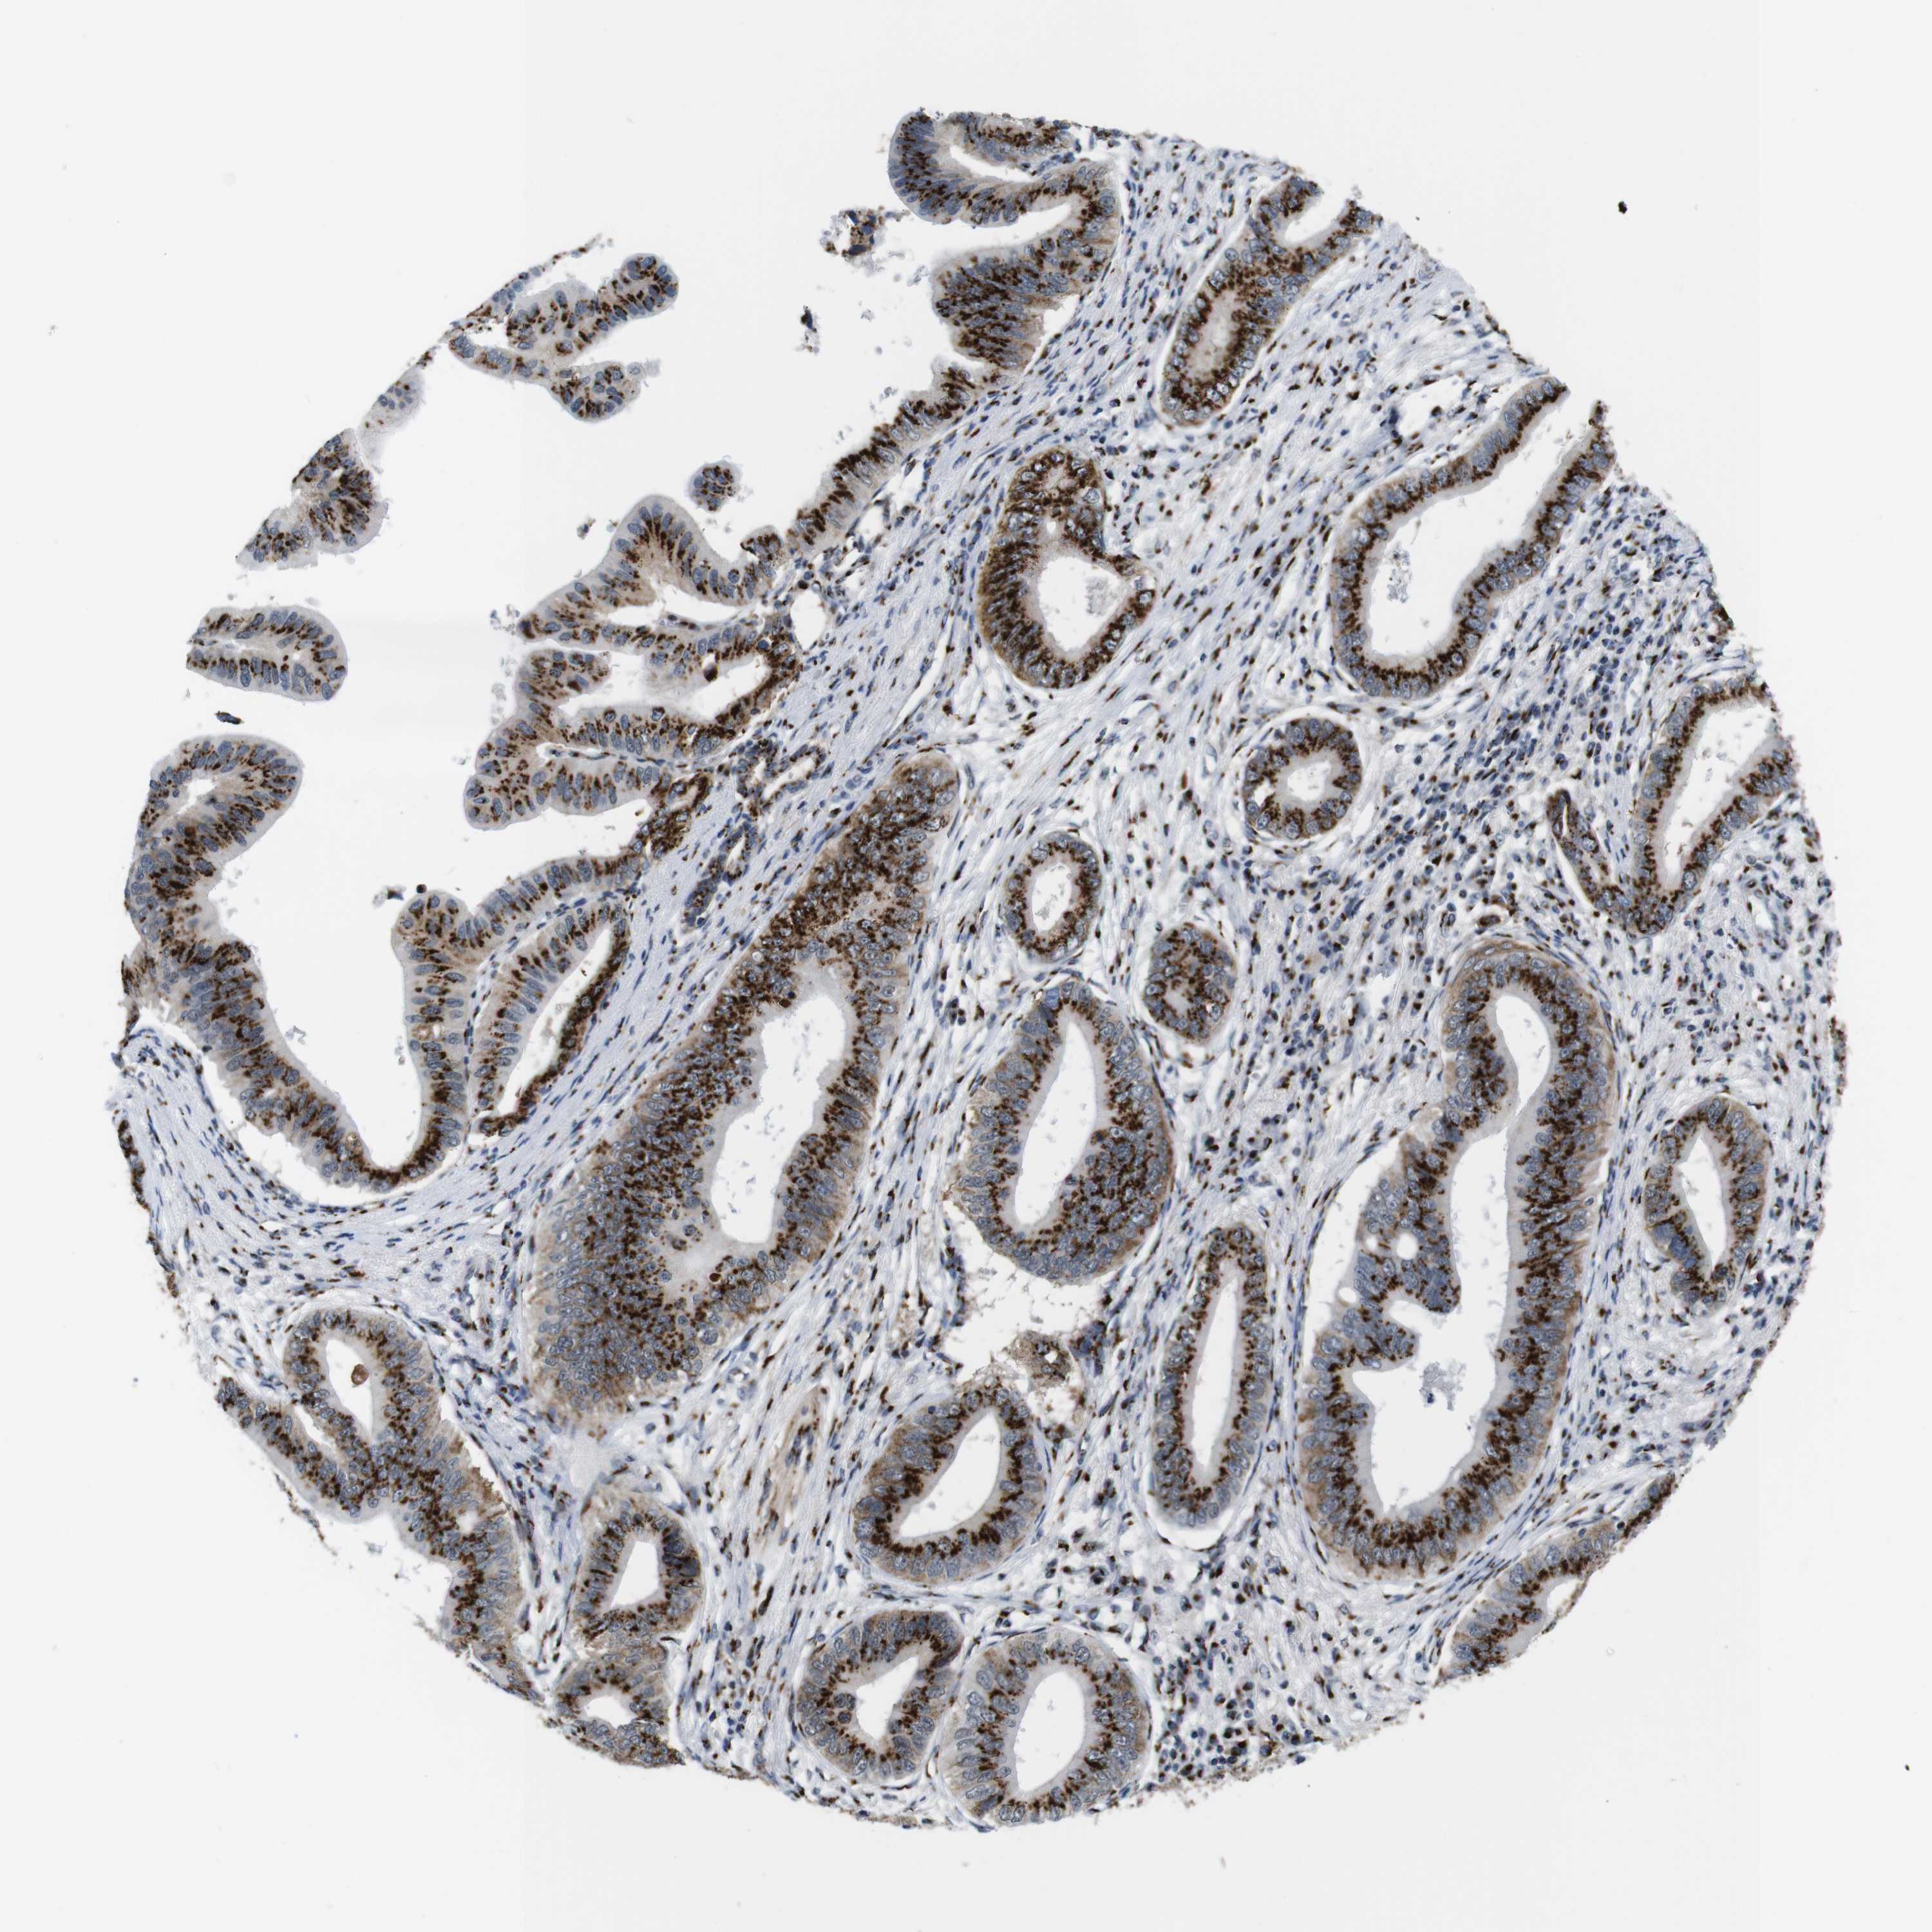

PANCREATIC CANCER - Protein expressioni

A mouse-over function shows sample information and annotation data. Click on an image to view it in a full screen mode. Samples can be filtered based on level of antibody staining by selecting one or several of the following categories: high, medium, low and not detected. The assay and annotation is described here.

Note that samples used for immunohistochemistry by the Human Protein Atlas do not correspond to samples in the TCGA dataset.

Antibody stainingi

Antibody staining in the annotated cell types in the current human tissue is reported as not detected, low, medium, or high, based on conventional immunohistochemistry profiling in selected tissues. This score is based on the combination of the staining intensity and fraction of stained cells.

Each image is clickable and will lead to virtual microscopy that enables deeper exploration of all samples and also displays staining intensity scores, fraction scores and subcellular localization as well as patient and tissue information for each sample.

Antibody HPA012609

Antibody HPA012723

Antibody CAB011489

Staining

High

Medium

Low

Not detected

Intensity

Strong

Moderate

Weak

Negative

Quantity

>75%

75%-25%

<25%

None

Location

Nuclear

Cytoplasmic/membranous

Cytoplasmic/membranous,nuclear

Adenocarcinoma, NOS